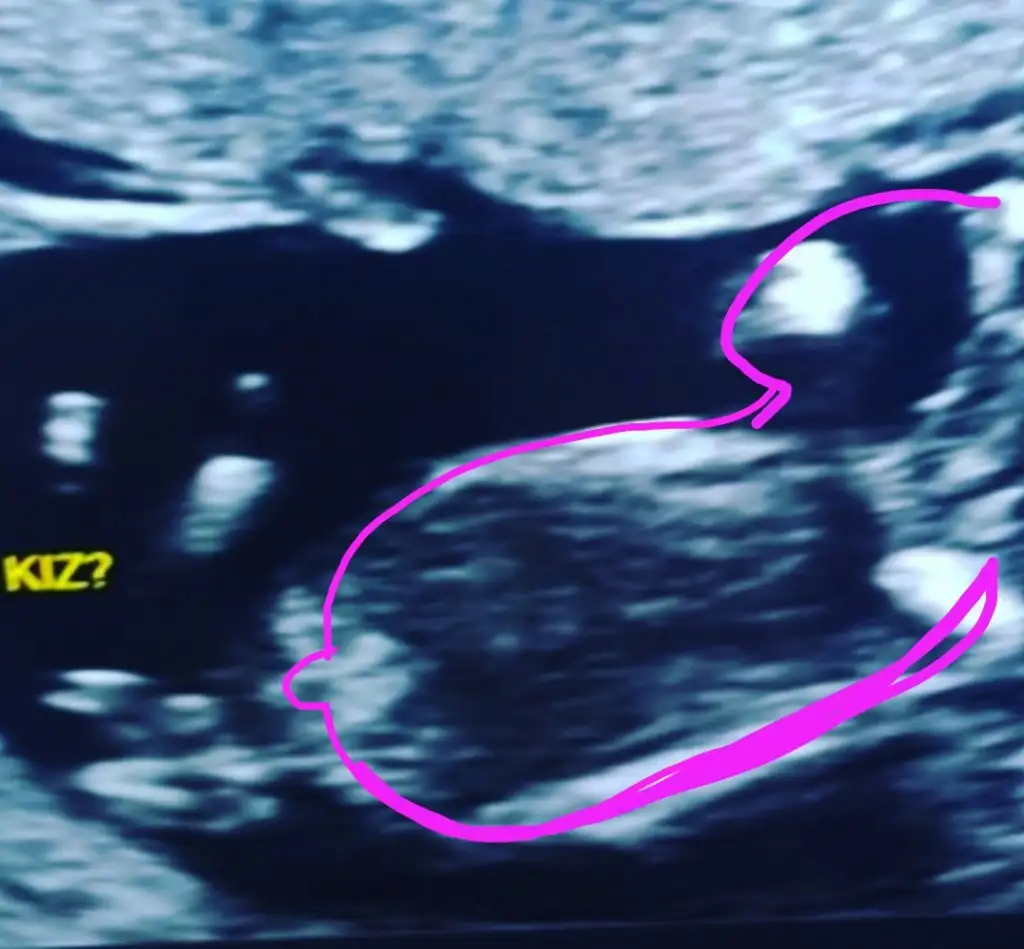

Kız gibi diyorum nubu tam düz görünmuyor ama dikte değil sabahki erkek yorumunu geri aldım cizdim şimdi 🙈☺️ tam karşıya bakıyor umarım yanilmiyorum 🙈

Başka USG varsa teyit edeyim 🙈

Burada da karşıya bakıyor tam paralel değil dikte değil üsteki USG ile ayni nub gibi oyum kız gibi diyorum olursa 13+ paylaşın 🙈